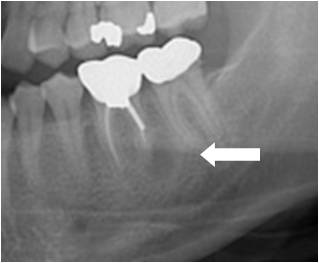

치근단 부위 부종

근단 주위 농양(Periapical abscess with sinus)

치근낭(Radicular cyst)

관련질환

근단 주위 농양